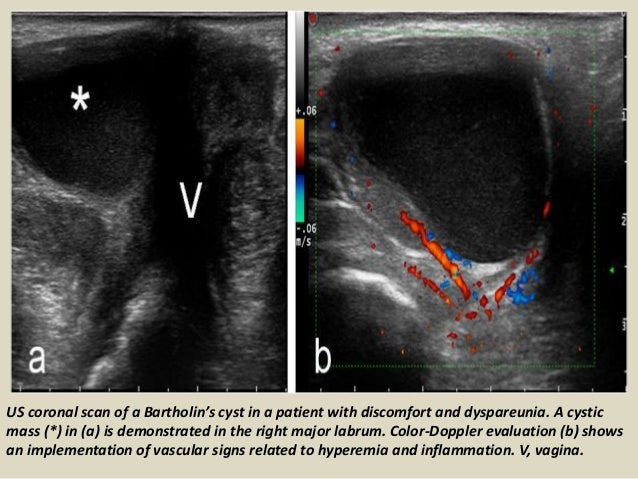

presentation1pptx ultrasound examination of the uterus and ovaries 23 638, image source: www.slideshare.net